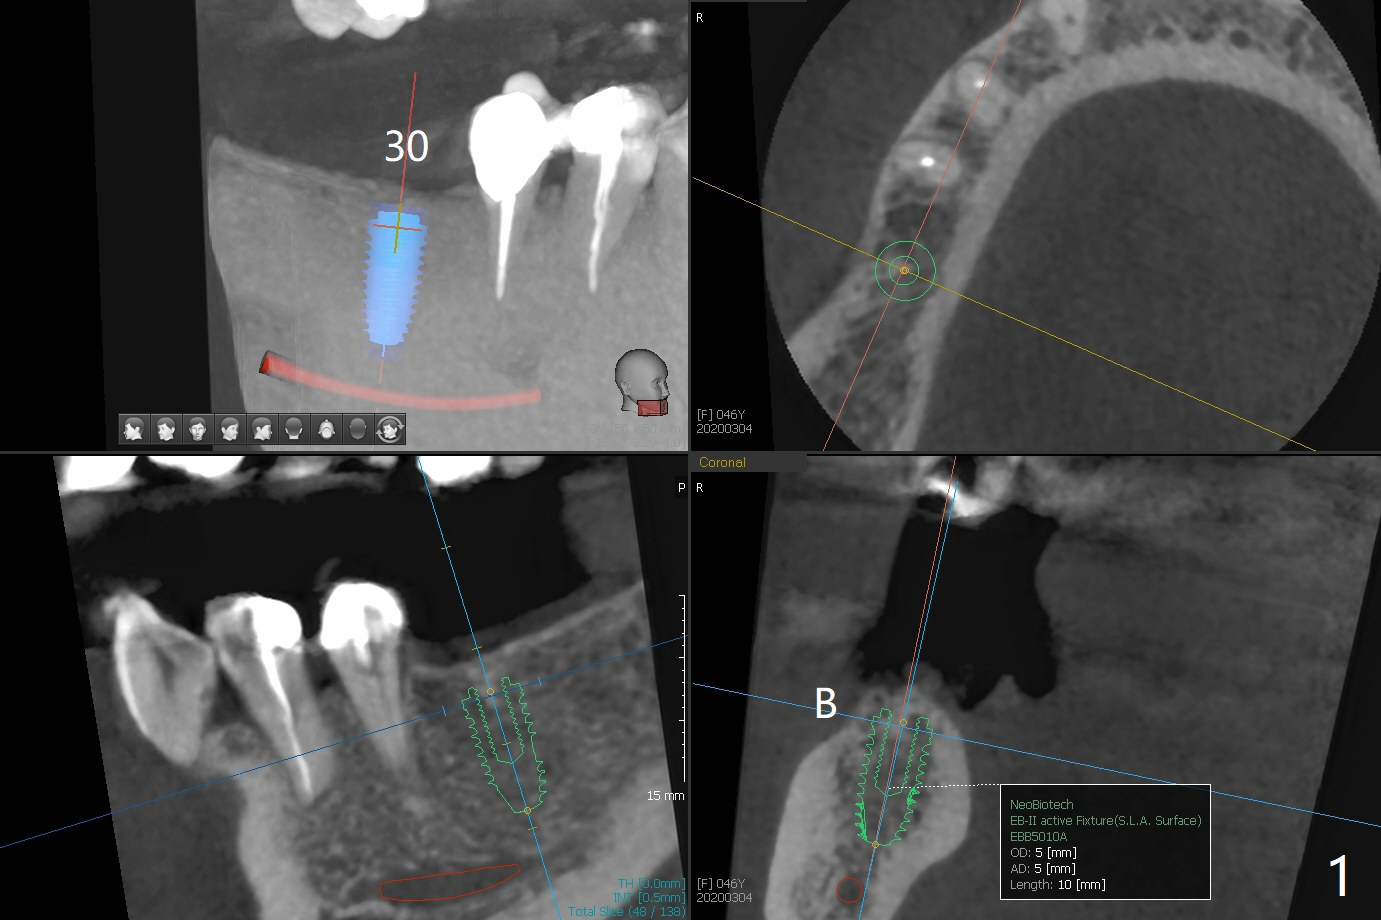

A 46-year-old woman returns for preparation for an implant at #30 two years 3 months post #6 (M) and 7 implant crown cementation (Fig.1). With the moderate ridge, implant placement should be easy, but the vertical restorative height is limited due to the opposing supraerupted molar. If the keratinized gingiva is narrow, make incision instead of tissue punch. In fact the crestal cortex is the most important structure associated with implant placement and should be carefully studied prior to implant design (Fig.2 arrowheads in 3D view as well as the sagittal and coronal (Fig.3) sections). If socket preservation were done, the ridge would be wider and taller (Fig.4 yellow dashed line) with possible thicker cortical bone.